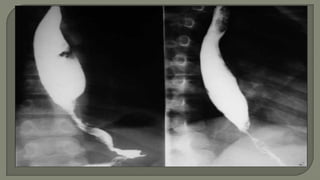

 Barium Swallow

o Dilated, tortuous, oesophagus that smoothly

tapers down at the OGJ giving the "Bird's

beak" appearance.

o absence of gas in the fundus of the

stomach.

o weak, irregular, uncoordinated or absent

peristalsis on fluoroscopy.

 Barium Swallow oDilated, tortuous, oesophagus that smoothly tapers down at the OGJ giving the "Bird's beak" appearance. o absence of gas in the fundus of the stomach. o weak, irregular, uncoordinated or absent peristalsis on fluoroscopy.